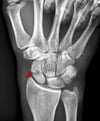

Переломи човноподібної кістки

Переломи човноподібної кістки зазвичай виникають внаслідок надмірного розгинання зап’ястка. Вони можуть бути непомітні на первинних рентгенограмах. Ускладнення можуть бути тяжкими.

На початку виконується звичайна рентгенографія (в передньо-задній, бічній та косій проекціях), хоча досить часто рентгенівські знімки є нормальними. Лише близько 70% переломів човноподібної кістки помітні на початкових рентгенограмах (1).